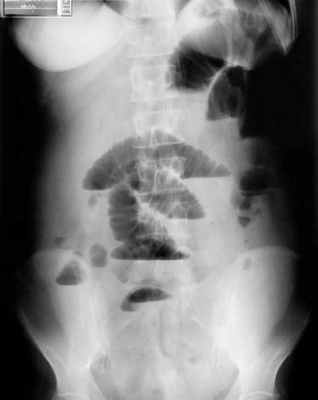

Рентгенологическое исследование является основным специальным методом диагностики ОКН. При этом выявляются следующие признаки:

- Чаша Клойбера – горизонтальный уровень жидкости с куполообразным просветлением над ним, что имеет вид перевернутой вверх дном чаши. При странгуляционной непроходимости могут проявляться уже через 1 час, а при обтурационной непроходимости — через 3-5 часов с момента заболевания. Количество чаш бывает различным, иногда они могут наслаиваться одна на другую в виде ступенчатой лестницы.

- Кишечные аркады. Получаются, когда тонкая кишка оказывается раздутой газами, при этом в нижних коленах аркад видны горизонтальные уровни жидкости.

- Симптом перистости (поперечная исчерченность в форме растянутой пружины) встречается при высокой кишечной непроходимости и связан с растяжением тощей кишки, имеющей высокие циркулярные складки слизистой. Контрастное исследование желудочно-кишечного тракта применяется при затруднениях в диагностике кишечной непроходимости. Больному дают выпить 50 мл бариевой взвеси и проводят динамическое исследование пассажа бария. Задержка его до 4-6 часов и более дает основание заподозрить нарушение двигательной функции кишечника.

Рентгенологическая диагностика острой кишечной непроходимости. Уже через 6 ч от начала заболевания имеются рентгенологические признаки кишечной непроходимости.

На рентгенограммах, полученных в положении стоя или лежа на боку, обычно видны горизонтальные уровни жидкости и газа (рис. 2). Рисунок 2. Обзорная рентгенограмма брюшной полости. Видны чаши Клойбера, уровни жидкости. Заполненные газом кишечные петли имеют вид опрокинутых чаш (чаши Клойбера). Они появляются при странгуляции через 1-2 ч после начала заболевания, при обтурации - через 3-5 ч. По размерам чаш Клойбера, их форме и локализации можно судить об уровне непроходимости.

При тонкокишечной непроходимости чаши Клойбера небольших размеров, ширина горизонтального уровня жидкости больше, чем высота столба газа над ним. Обычно наблюдается большое количество горизонтальных уровней с изменением их расположения в течение времени и перемещением жидкости из одной петли в другую. Горизонтальные уровни жидкости ровные. На фоне газа хорошо видны складки слизистой оболочки (складки Керкринга), принимающие форму растянутой спирали.

При непроходимости тощей кишки горизонтальные уровни жидкости локализуются в левом подреберье и эпигастральной области. При непроходимости в терминальном отделе подвздошной кишки уровни жидкости расположены в области мезогастрия.

При тонкокишечной непроходимости, кроме чаш Клойбера, на рентгенограммах видны растянутые газом кишечные петли, принимающие форму «аркад» или «органных труб», похожих на перевернутые буквы J и U.

При динамической паралитической непроходимости, в отличие от механической, горизонтальные уровни жидкости наблюдаются одновременно как в тонкой, так и в ободочной кишке. Перемещения кишечных уровней со временем из одного колена кишки в другое не наблюдается. При динамической спастической непроходимости по ходу тонкой кишки видны мелкие чаши Клойбера, расположенные цепочкой слева сверху вниз и вправо.